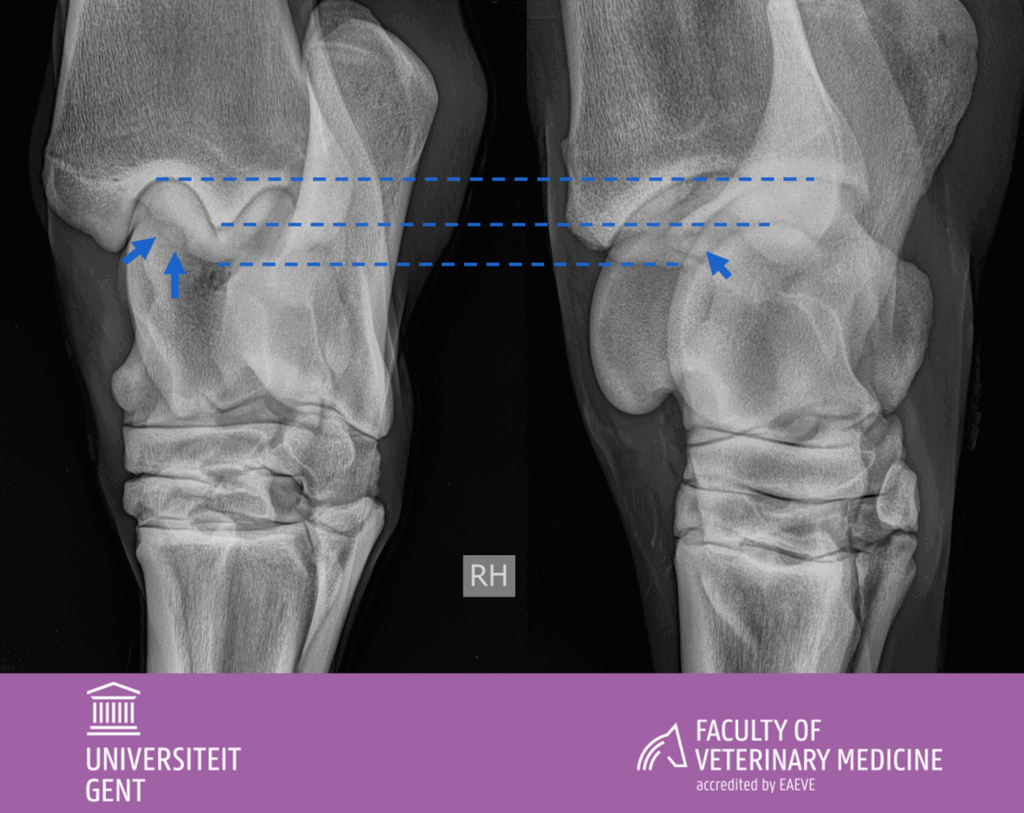

Radiografieën de rechter sprong (LM, DL-PlMO en DM-PlLOO) :

Er is inderdaad weke delen zwelling ter hoogte van de dorsomediale recessus van het tarsocruraal gewricht zoals aangegeven op het klinisch onderzoek.

Een goed afgelijnde indeuking is zichtbaar ter hoogte van het craniomediaal aspect van de intermediaire kam van de cochlea tibiae, met een klein geassocieerd fragment.